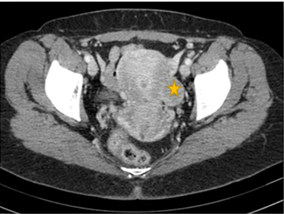

Transvaginal ultrasound showed a 11x10x9 cm uterine tumour suggestive of subserous myoma FIGO 7, located in the left lateral fundus of the uterus (Figure 1). Reviewing her medical history, we found a computed tomography scan 5 years earlier with a 4 cm uterine fibroid in the same location (Figure 2).

Figure 1 5 months before CT abdominal: Uterine posterior myoma of 40 mm.

Figure 2 Current pelvic ultrasound. Uterine myoma of 110 mm.